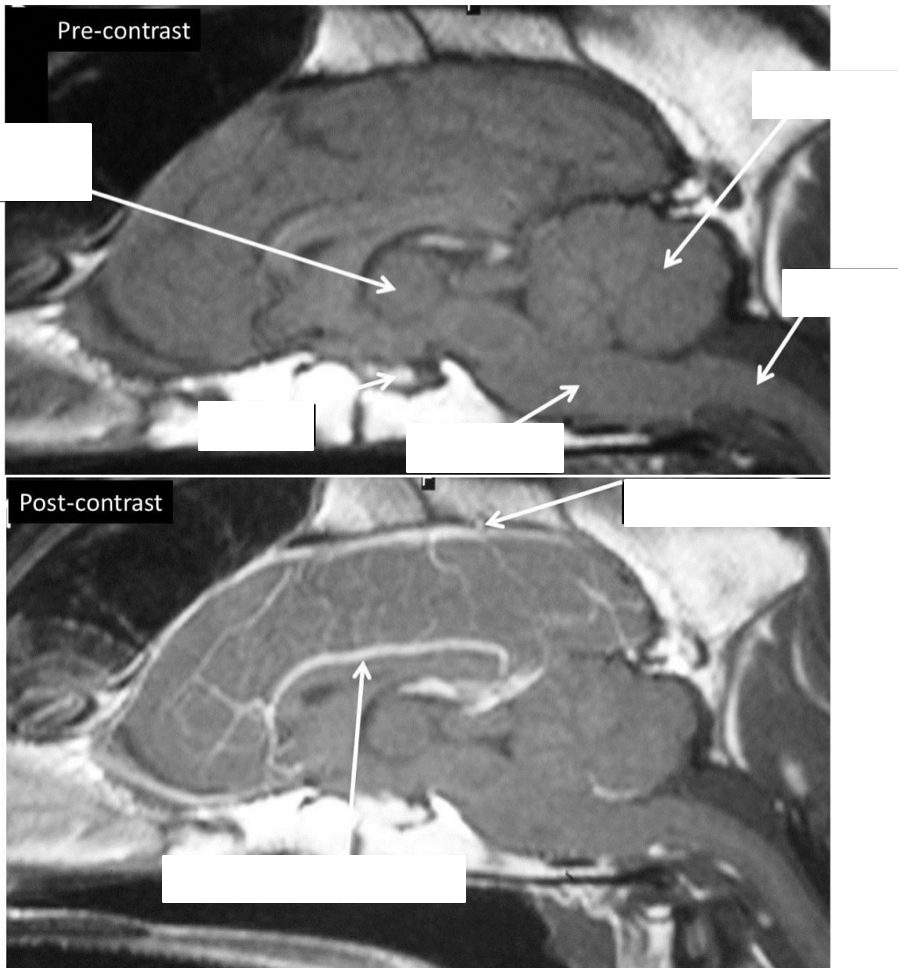

what are these structures and what weight are the scans

T1-weighted sagittal scans (fluid will be dark)

before and after admin of contrast

increased visibility of blood vessels within brain

identify the lateral ventricles, pituitary, cerebellum, cerebral hemispheres, brainstem, eyeballs

identify the structures

identifty the interthalamic adhesion, brain stem, spinal cord